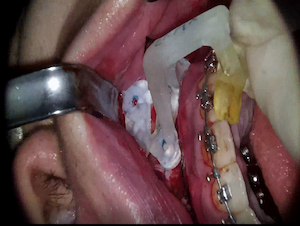

Root Membrane with R2GATE

#12,#21,#23,#26,AnyRidge,Digital Guided Surgery,Dr. Konstantinos Siormpas,Flapless,Guided surgery,Immediate Placement,Maxillary Anterior,Maxillary Posterior,R2GATE Guide,R2GATE Universal Kit,Root Membrane,Root Membrane Kit,video,Xpeed